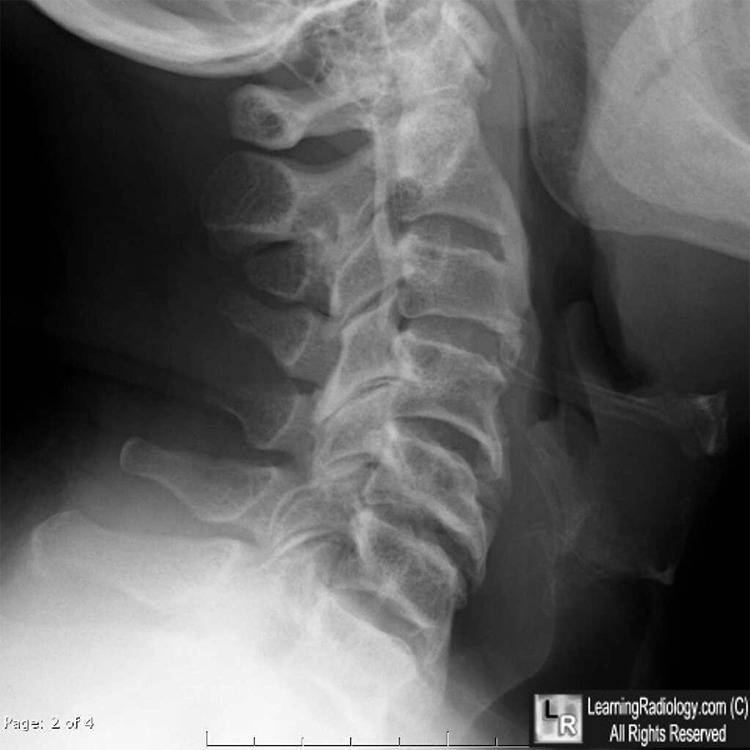

Ossification of the Posterior Longitudinal Ligament (OPLL). Above:Linear ossification just posterior to the posterior border of the cervical vertebral bodies (white arrows). Below: Sagittal reconstruction of cervical spine CT on left shows same flowing ossification (yellow arrow); axial CT demonstrates the ossified posterior longitudinal ligament (blue arrow).

- Linear ossification immediately posterior to vertebral body in canal

- May be continuous (spans several bodies and intervening disc spaces), segmental (occupies back of body but spares disc spaces) or both

- Predominantly in high cervical spine

- CT is best at demonstrating ossification